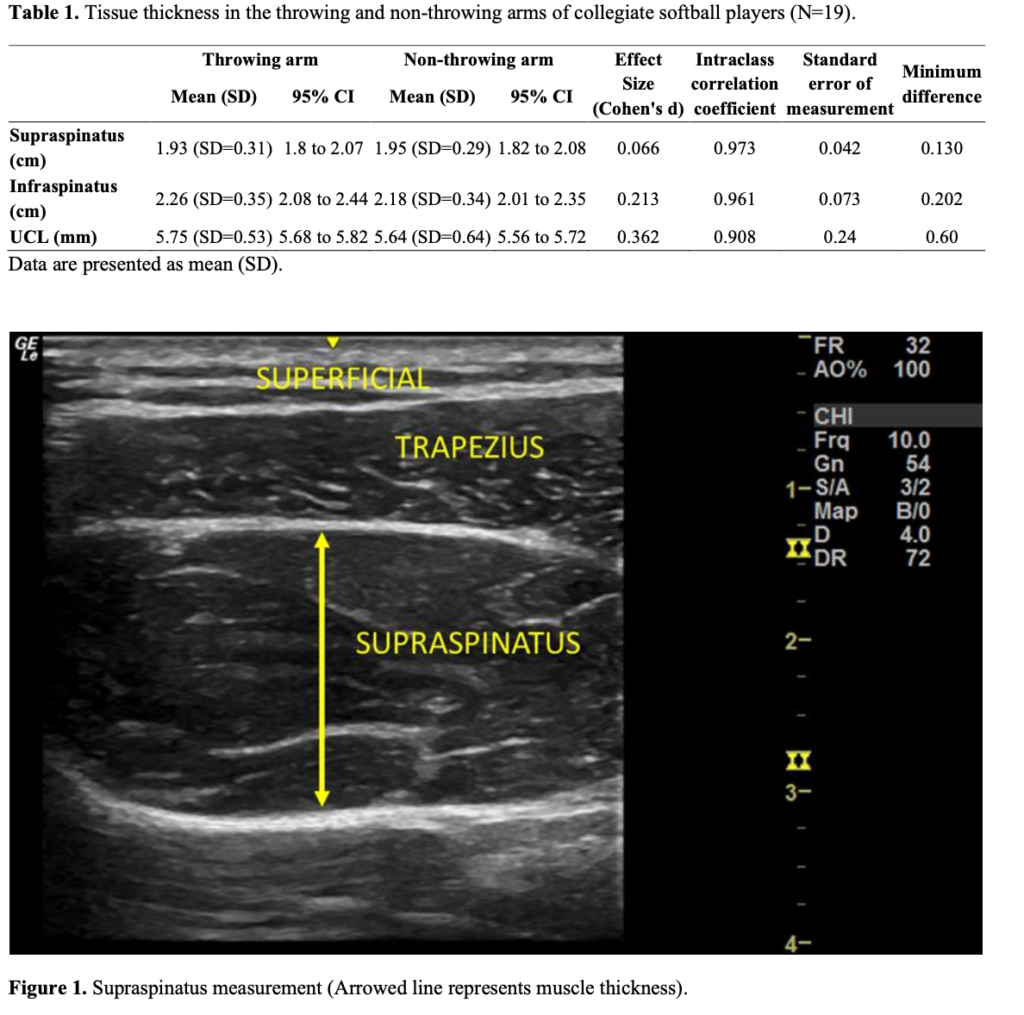

In a brand-new article, Burton et al. (2025) studied 19 NCAA Division I female collegiate softball players to determine whether repetitive overhead throwing led to long-term structural changes in the shoulder and elbow. Only non-pitchers were included, since pitchers primarily throw underhand. Using ultrasound imaging, the researchers measured the thickness of three structures in both arms: the supraspinatus muscle, the infraspinatus muscle, and the ulnar collateral ligament (UCL). All measurements were taken with the athletes seated and relaxed, following standardized imaging procedures to ensure accuracy. Two images were collected for each structure and averaged. The throwing arm was compared to the non-throwing arm within each athlete using paired t-tests to see if chronic throwing caused tissue thickening.

- No significant differences in tissue thickness between the throwing and non-throwing arms

- Supraspinatus thickness was nearly identical between arms (p = 0.401)

- Infraspinatus thickness showed no meaningful difference (p = 0.236)

- UCL thickness was similar in both arms (p = 0.171)

- Effect sizes were small, indicating minimal structural asymmetry

- Ultrasound reliability was high (ICC values > 0.90), showing measurements were consistent